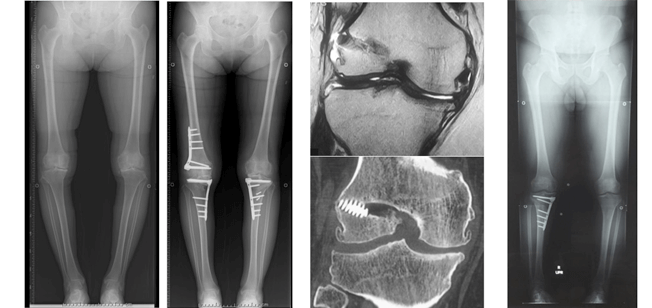

前十字靱帯損傷は、スポーツ活動においてパフォーマンスを著しく低下させるだけでなく、2次性変形性膝関節症を引き起こします。その頻度は、12年で63%、30年で86%とも言われております。膝前十字靭帯機能を再獲得するため、我々は、解剖学的な靭帯付着に正確に長方形骨孔を作成した骨付膝蓋腱を用いた方法で再建しております。前十字靱帯損傷には半月板損傷や軟骨損傷を合併することが多く、半月板損傷には半月板縫合術を、軟骨損傷には骨穿孔術や骨軟骨移植術、自家培養軟骨移植術を併用しております。

半月板は、線維軟骨でできており、膝関節においてはクッションの役割があります。半月板の損傷が起こると続いて軟骨損傷が生じ、時間が経つと関節の変形が生じてきます。

我々は、軟骨機能を温存するため、inside-out法による強固な縫合を、関節鏡を用いて行っております。より強固に縫合するため特殊な縫合方法で行っております。下肢アライメント不良がある膝に対しては、アライメント矯正手術を併用した半月板縫合術も行う場合もあります。

我々は、変形性膝関節症に対して関節温存手術を検討する場合、患者さんの下肢アライメント解析を行い、それぞれの変形に応じて種々の骨切り術(open wedge 型高位脛骨骨切り術、closed wedge 型高位脛骨骨切り術、大腿骨遠位骨切り術、脛骨顆外反骨切り術)を駆使し、治療にあたっております。関節鏡も併用し、骨髄刺激法や半月板縫合など、適宜処置を追加します。

硝子軟骨による軟骨再生は、整形外科医にとっても夢の治療であった。それが、2015年より保険収載され、臨床の現場で使用できるようになった。適応は4cm2以上の軟骨損傷で、1回目の手術で、膝の非荷重部の関節軟骨から関節鏡を用いて採取し、28日後に2回目の手術を行い、出来てきた培養軟骨を移植するものである。アライメント異常がある場合は、骨切り術なども併用することもある。